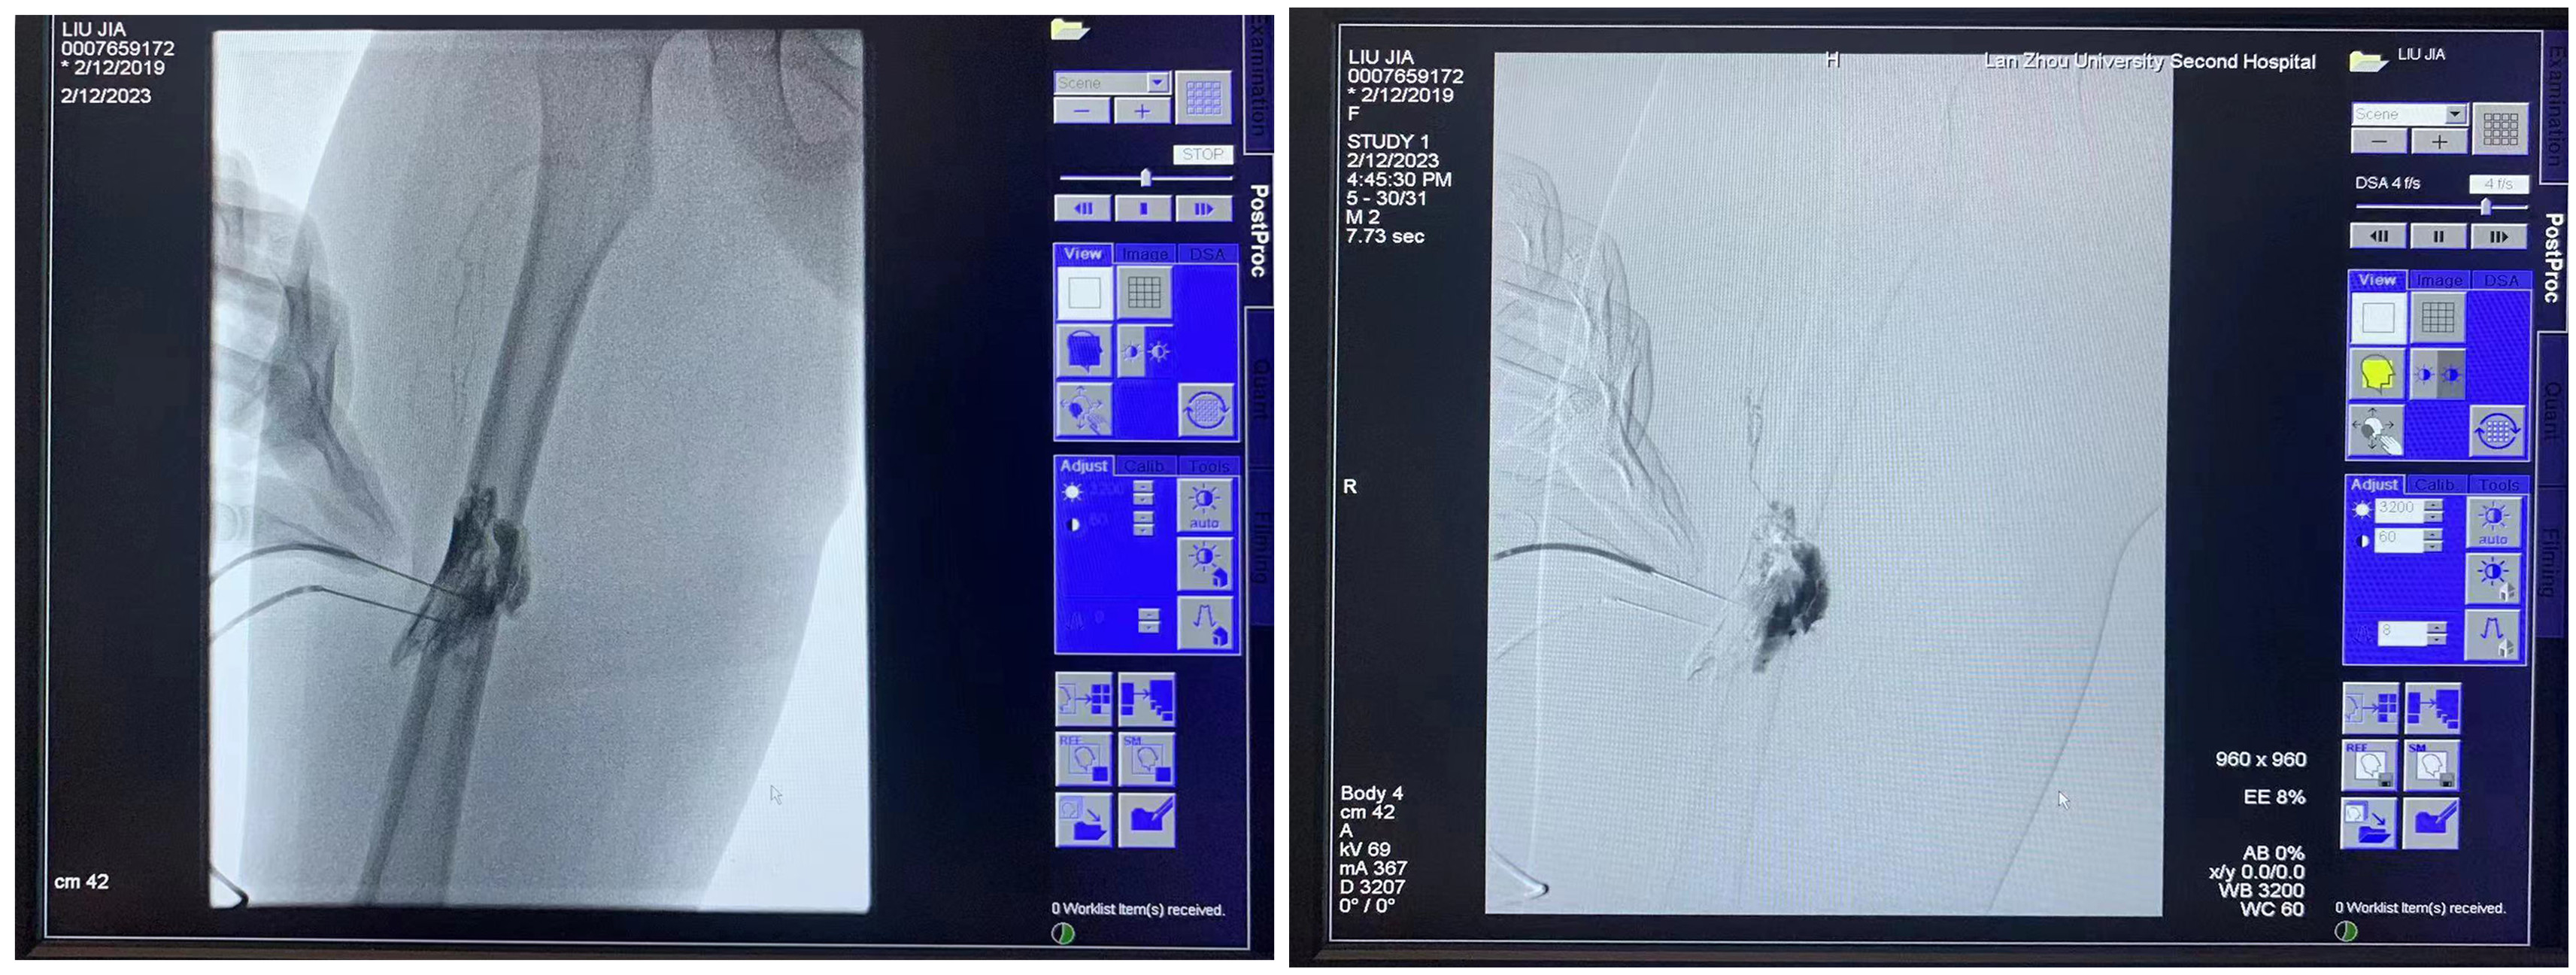

两位患儿就诊于兰大二院小儿心血管科,结合病史,检查、检验结果及临床表现分别诊断为淋巴管畸形和静脉畸形。针对患儿病情的复杂程度和特殊情况,经评估讨论后拟实施DSA引导下经皮介入硬化治疗术,并邀请四川大学华西第二医院胡梵教授进行技术指导。术中,通过DSA引导局部注入泡沫硬化剂对病变部位进行硬化治疗,手术历时2.5个小时,术中患儿病情稳定,术后恢复良好,2天后康复出院。